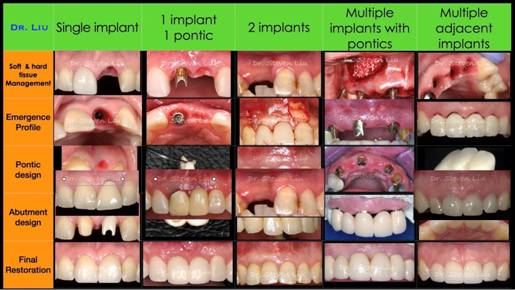

外科學觀點(Surgical Perspectives)

深入探討先進植牙手術、軟硬組織臨床進階技巧操作,確保骨量維持與降低術後併發症風險。

修復學觀點(Restorative Perspectives)

分析贋復設計原則、材料選擇以及負載控制,以確保修復體與周圍軟硬組織的協調穩定,並兼顧長期臨床耐用性與功能完整性。